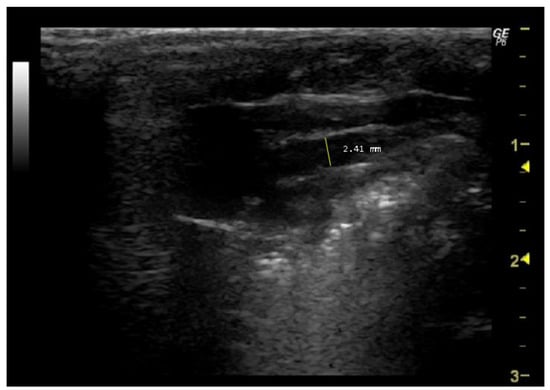

- How to measure pulmonary artery diameter